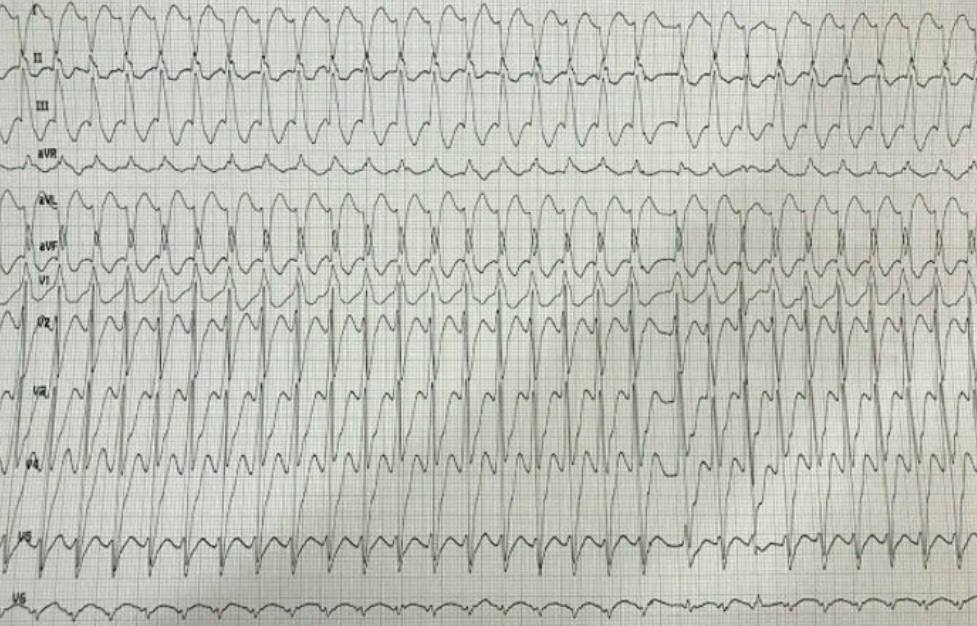

This ECG pattern is diagnostic of? A. Left bundle branch block B. Acute myocardial infarction C. Wolff-Parkinson-White (WPW) syndrome D. Hyperkalemia #NEETPG #MedTwitter Dr. Akhil 🇮🇳 Dr. Priyam Bordoloi Dr. Shiv_Kumar Antonio Arroyo, MD. Medico Cirujano. Dr. Medica🩺 MedLearn Hub Medzonetv

What is the first step in the management of a hemodynamically stable patient with the following rhythm shown on ECG? Options: A. IV Amiodarone B. Carotid massage C. Chest compressions D. Synchronized cardioversion #MedTwitter #Medx Dr. Akhil 🇮🇳 Dr. Priyam Bordoloi Dr. Shiv_Kumar